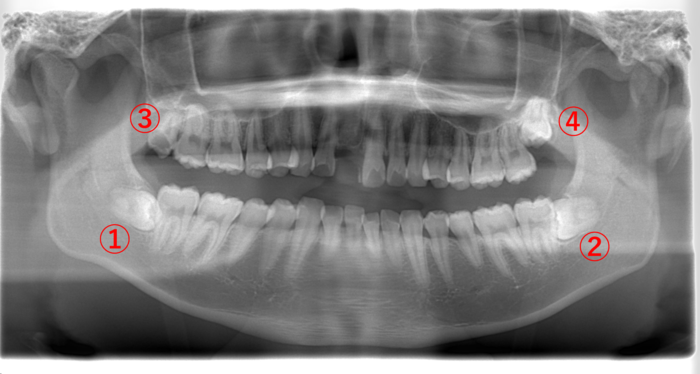

| 主訴 | 右上の親知らず(画像③)が急に痛み始めた。 |

画像③の親知らずを見てみると黒く透けています。虫歯になると歯が溶けて柔らかくなるので、レントゲンでは黒く写ります。虫歯が歯の神経に達すると痛みが強くなります。

③の親知らずを抜歯して、①の親知らずも抜きたいところですが、③の親知らずの痛みが強いこともあり、一緒に抜歯せずに後で③の親知らずを抜く方が良いと説明しました。

親知らず以外の歯に関してはかなりきれいに磨けていました。奥にある親知らずの歯ブラシが難しいことがわかります。

痛みが強い歯は、その状態により対合する歯を一緒に抜くことができないこともあります。

| 主訴 | 左上の親知らず(画像④)が痛くて我慢ができない。どちらかというと鋭い痛みがある。 |

親知らずが生えることによる痛みとは異なる「鋭い痛み」の原因究明のため、まずはレントゲンを撮影しました。

画像④の親知らずに大きな黒い虫歯の影が見えます。虫歯になると歯が溶けて柔らかくなるので、レントゲンには黒く写ります。

また、1番奥にある親知らずまで歯ブラシが届かずに、気付いたら虫歯が大きくなっていたことが予想されます。

虫歯の痛みが強い時に親知らずを抜こうとしても麻酔が効きにくいことが予想され、患者さまの負担を考えると無理に親知らずを抜かないことも選択肢のひとつになります。

そこで、この患者さまには、今すぐに親知らずを抜くのではなく、まずは虫歯の痛みをとる治療を優先させて、虫歯の痛みが無くなってから親知らずを抜きましょうと説明しました。

画像④の親知らずを抜いた場合、下の➁の親知らずを抜かずに放置すると上に伸びて来て、かみ合わせの邪魔をすることがあります。

そのため、上下同時に親知らずを抜くか、④の親知らずを抜いてから➁の親知らずを抜くか、どちらかになります。また、右上④の親知らずがないため、②と④の抜歯後、①の親知らずを抜きます。

| 主訴 | 数日前より右下の親知らず(画像①)周りの歯ぐきが急に腫れ始めて、みるみる内に膨らんだところを誤って噛んでしまい、出血が止まらなくなった。 |

| 歯ブラシ | 親知らずは、真っ直ぐ生えているが、歯ぐきが中途半端に被っているために、奥までなかなかキレイに磨くことができない状態。 |

親知らずが生える過程で、このように歯ぐきを押すという現象が起こることがあります。

中途半端に親知らずが顔を出すと中に汚れが溜まりやすくなります。そこが炎症を起こして腫れていたところ、歯ぐきを誤って噛んでしまったため、出血が止まらなくなったという状態です。

今後、画像➁の親知らず周りも腫れることが予想され、同じように噛んで出血するというパターンも考えられるため、できれば4本とも抜いた方が良いでしょう。

初回は、止血処置、抗生剤の投与と服用で腫れを引かせ、後日、画像①の親知らずを抜きました。

| 主訴 | 右下の親知らず(画像➁)が、腫れて痛い。 |

親知らず以外はきれいに磨けていますが、親知らず周囲は、磨けていないため、画像①の親知らず周りの歯ぐきが腫れて炎症を起こしていました。

この腫れた歯ぐきを上の歯で噛んでいる状態のため、食事の際は歯ぐきを噛んでしまい、食事が満足に摂れないと思います。

当日は、親知らずを抜かずに歯ぐきを切除し、痛み止め・抗生物質を処方しました。後日、炎症が治まったことを確認し、親知らずを抜きました。

➁の親知らずは、歯ぐきから顔を出していないため、抜かずに様子を見ることになりました。

画像①の親知らずが真横に生えていて、手前の⑤の歯との間に隙間があります。ここに食べかすが入り込むとどんなに歯を磨いても取れません。取り除かれない食べかすが腐り、口臭の原因となっていると思われます。

早めに抜くことで口臭はなくなると思われます。また➁の親知らずも汚れが溜まりやすそうなので、口臭の原因となる可能性があります。

そして、③の親知らずは、黒く透けていることからして虫歯になっています。

このことから、歯ブラシが親知らずの奥まで十分に届いていないことが考えられます。

この場合、右側上下(①と③)と②の親知らずを抜くことをオススメします。

④の親知らずは、歯ぐきが被ったまま出てこないのであれば積極的に抜かず様子を見ても良いですし、もし全部抜いてスッキリしたいのであれば、抜いた方が良いと思います。

| 主訴 | 親知らずに食べ物が挟まる。 |

画像➁の親知らずは横向きに生えているため、食べる度に手前⑤の歯との隙間に食べ物が挟まり、虫歯になっています。

このような場合は、早めに親知らずを抜いて手前⑤の歯の虫歯を治療した方が良く、また②の親知らずを抜くと上の④の親知らずが下がってくるため、一緒に抜いた方が良いです。

そして反対側①の親知らずは、顔を出しているので、歯ブラシが上手くできないのであれば抜いた方が良いこと、③に関しては、顔を出してない親知らずのため、無理して抜かなくても良いと説明しました。

画像①と③の親知らずは、真っ直ぐ生えていますが、2〜3日前より①の親知らず周りの歯ぐきが腫れて痛いとのことでした。

奥まで磨くのは困難と判断し、①の親知らずを抜くことにしました。また説明として、対合歯がない③の親知らずは後々下に伸びてくることを考えると早めに抜いた方が良いことを伝えると同時に抜きたいと希望されたため、初診当日に①と③の親知らずを2本同時に抜きました。

④の親知らずは、歯ぐきから顔を出していないので、抜かずに様子を見ることになりました。

画像➁の親知らずが原因で、その手前の歯との間に虫歯ができてしまったケースです。

痛みの原因は親知らずではなく、手前の虫歯が神経に近いところまで達したため痛みが強くなってしまった、実に難しいケースです。

これ以上虫歯が進行した場合は、歯を抜かなければなりません。今回は幸いにして抜くほどには進行していなかったため、初日は②の手前の歯に神経の痛みをとる薬を入れて、2回目以降に根の治療をしました。

その後、ある程度落ち着いたところで、親知らずを4本一気に抜きました。